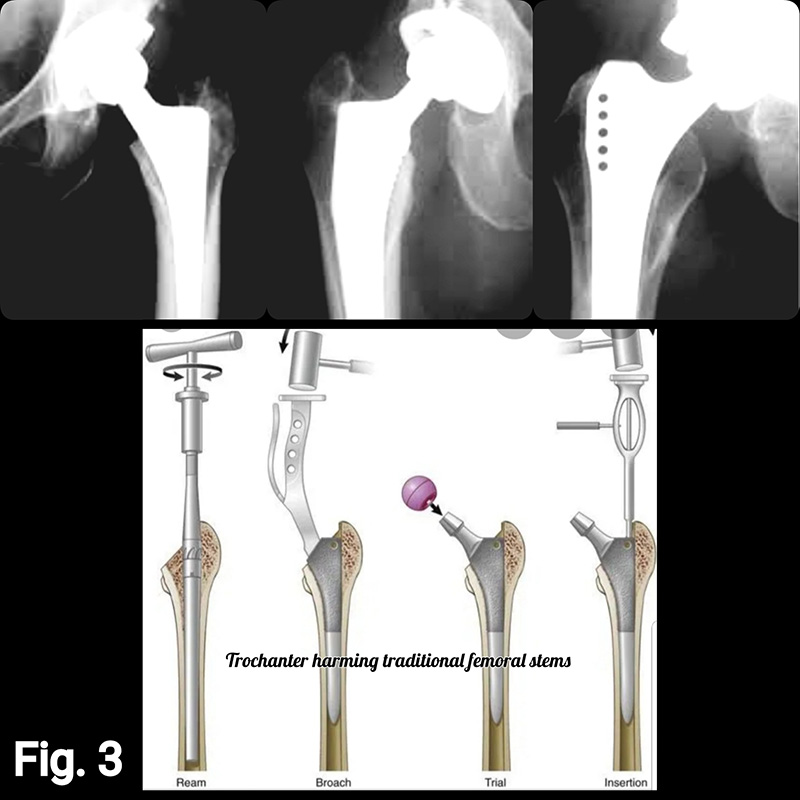

2 – Surgical convenience: The femoral neck is an obstacle to inserting a bulky device into the femoral canal. The insertion of the stem into the canal through the resected neck became easier the more bone you remove from the proximal femoral segment. (Fig. 3)